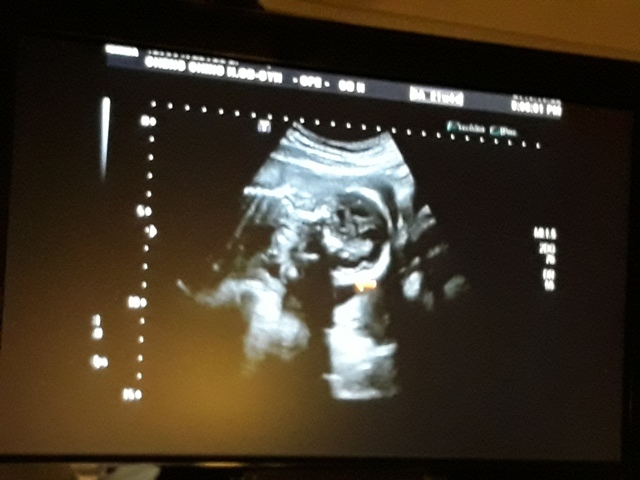

當小純進入診間看診時,我並沒有進去,因為小純說,有時男生不能進去,會被請出來。在外頭等待的我感到很緊張,不久之後,謢理人員請我進入診間,我嚇了一跳,想說發生什麼事了,進入之後,得知小純真的懷孕了,而且已懷了九星期又五天。看診的醫師說,驗孕棒第二條線淡淡的,沒想到胚胎照出來那麼大了,說Baby很健康。還說一閃一閃的是他的心跳,有頭、有手、有腳還有臍帶。小純後來說看了內心覺得很感動,才叫我一起進去看。

小純肚子裡的Baby超音波圖↓